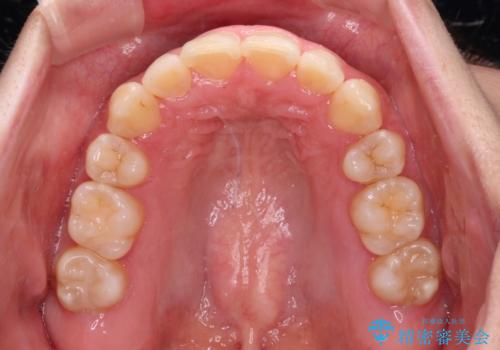

前歯のデコボコを短期間で解消 ワイヤー装置による抜歯矯正

当初予定は2年半程度と伝えていましたが、2年にも満たない期間で治療を終えることができました。